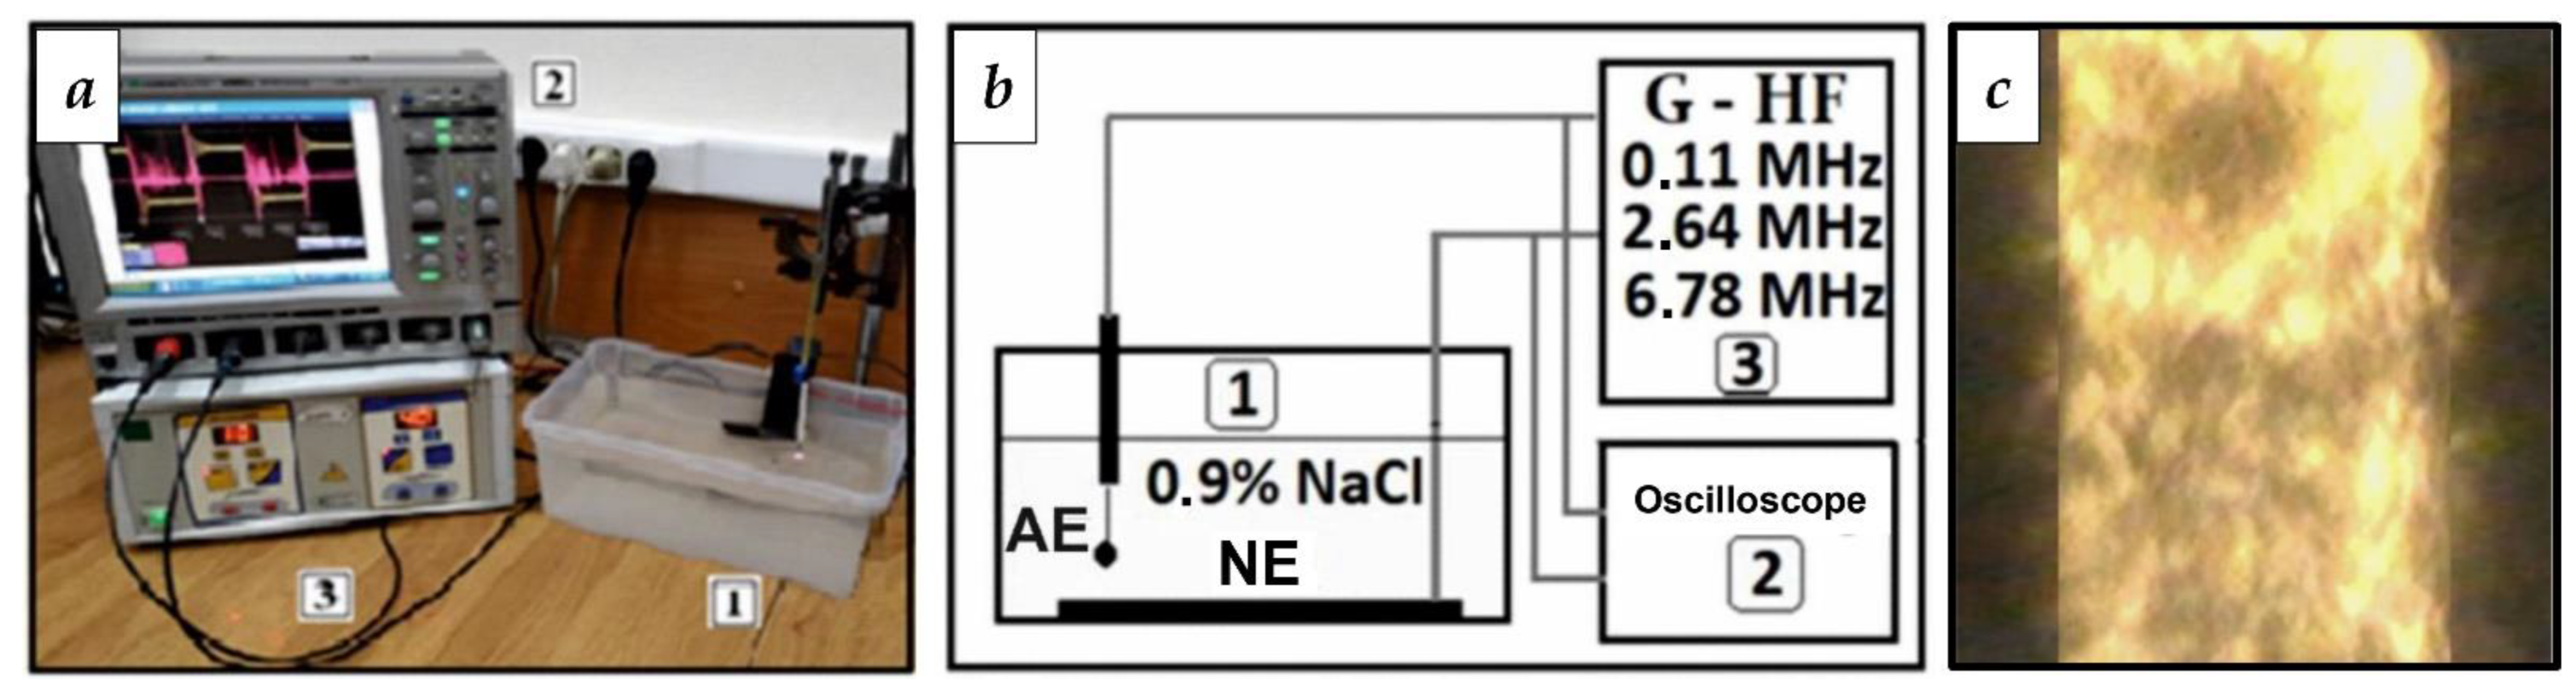

3.1. Selection of RF Current Parameters for WP Activation

- Belov, S.V.; Danileiko, Y.K.; Nefedov, S.M.; Osiko, V.V.; Salyuk, V.A.; Sidorov, V.A. Specific Features of Generation of Low-Temperature Plasma in High-Frequency Plasma Electrosurgical Apparatuses. Biomed. Eng. 2011, 45, 59–63. [Google Scholar] [CrossRef]